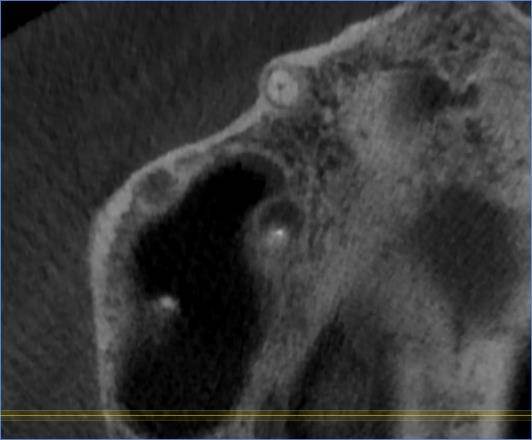

И есть второй зуб с проблемой около корней -16 (РФ зуб). Перед брекетами уже перелечивали корни в 2016 году.

Сейчас опять говорят надо заново перелечивать перед протезированием.

Имеет ли смысл? (а то так до бесконечности можно перелечивать и дешевле удалить было и имплантант поставить).16.jpg.c48b680915f979a9e4778f4248ff39c7.jpg16-1.jpg.c116f77ce054f4d184897797128c176a.jpg16-2.jpg.675bd02ec47e5582670209e0dc324a7f.jpg16-3.jpg.ece96fa59fc264e0e38c691000fc9780.jpg16-4.jpg.a269497c8968ad8cbd4d3c558c480d90.jpg16-5.jpg.e4f929dd96c9da3ce934b217da02a634.jpg16-6.jpg.260d3caac245b47f76f4f53ca38317c4.jpg